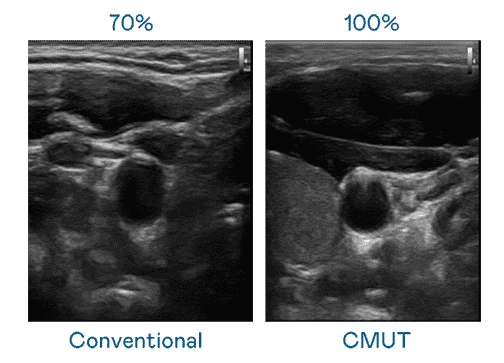

CMUT 技术是一种用电容式微机电元件来产生超音波讯号的技术。。。。与传统 PZT 压电式技术相比,,,CMUT 频宽增加 30%,,更宽频的超音波讯号让影像解析度大幅提升,,是实现高影像品质医疗超音波扫描、、促进精准医疗发展的关键技术。。

大频宽带来超清晰影像

超音波影像的解析度高低,,首先取决于探头能发出的讯号频宽。。。www.z6.com CMUT 可提供高清晰的超音波讯号,,,提供高频宽、、、、高灵敏度、、、、影像纹理细节更高的超音波影像,,,协助医护人员缩短影像判读时间及利用精准的医疗影像进行诊断。。。。